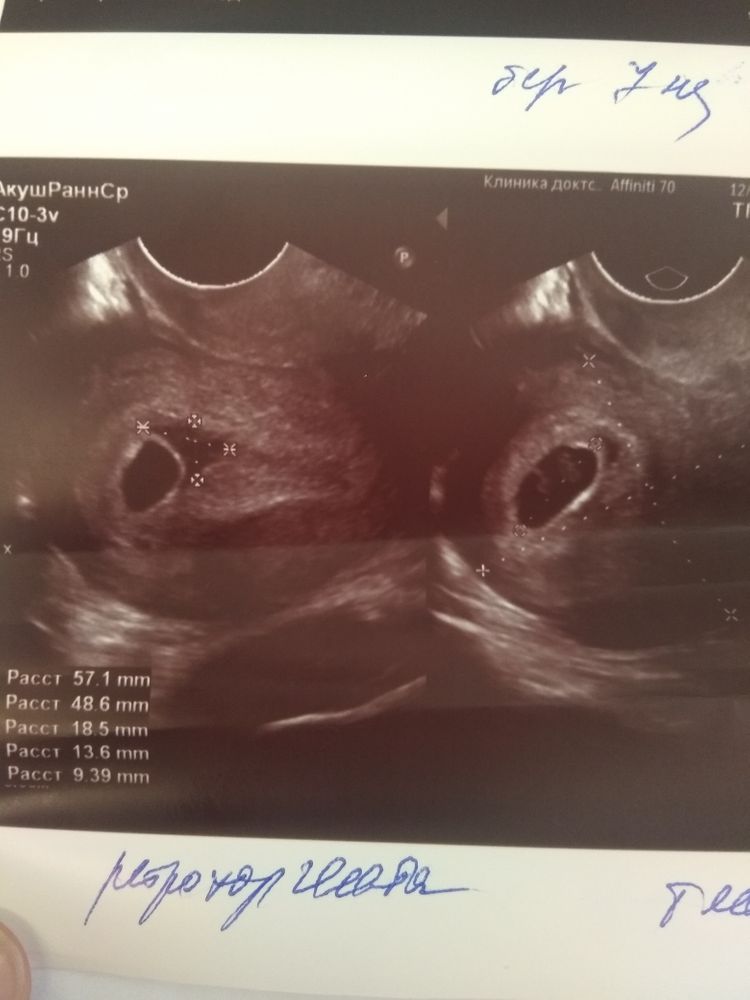

Ретрохороиальная гематома,7 недель...

Добрый день, девочки...проблемы и переживания продолжаются...Не буду вдаваться в подробности,дела обстоят так,была на УЗИ,срок соответствует (7нед),кто - 9.09 мм,час -148 уд. И гематома...

Гинеколог прописал :

Дюфастон- 1 т -2 р в день

Свечи с папаверином номер на ночь.

Магнелис В6 - 1 т утром,1 днём,2 вечером.

Воьензим - по 3 таблетки!-3 раза в день... ( как сказала желательно,и размахивала брошюрой перед носом,мол волшебный препарат,что меня смутило,так это дозировка,цена и то,что этот Бад чуть ли не от в его на свете)Кто то пил этот препарат,помог?